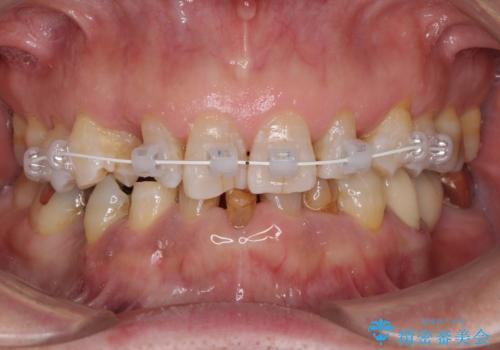

- 審美装置

上顎の矮小歯は隙間が多く、歯軸の傾斜も大きかったため、部分矯正により補綴治療前に歯の位置を整えることとしました。

前歯部はディープバイトという、上顎前歯が下顎前歯に深く覆い被さる咬合であったので、理想的には全顎矯正が必要となりますが、今回は患者希望により前歯部のみの部分矯正で対応しました。そのため下顎犬歯の神経を取り除くことになってしまったのは心残りであります。